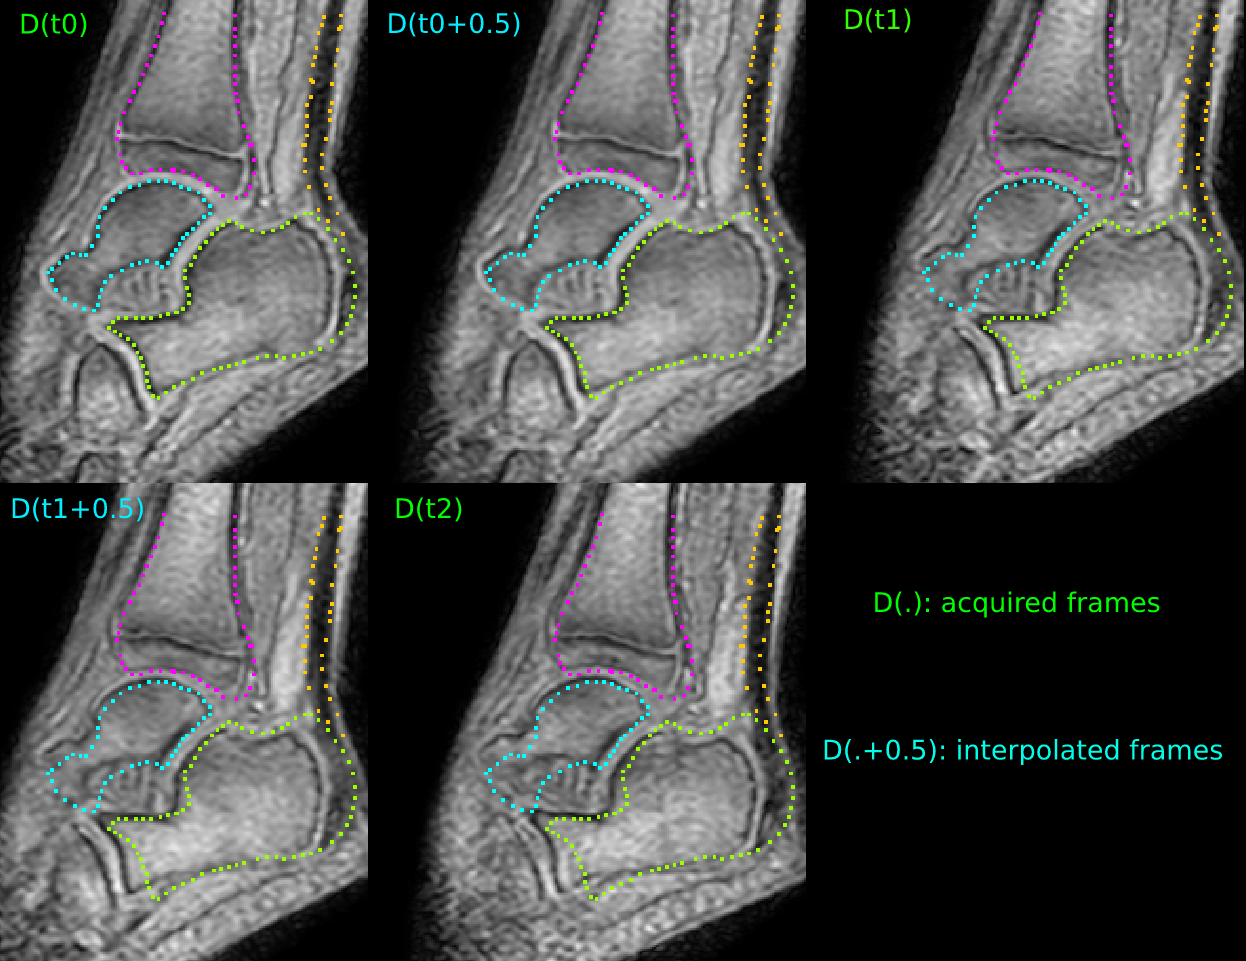

The exponential map of Eq (11) is computed within 2.22.22.2 seconds on a 352×352×63523526352\times 352\times 6 grid using the scaling and squaring method (which required 1.8 GB of RAM), and within nearly 444 seconds using the proposed eigendecomposition method (which required 0.8 GB of RAM). Figure 5 illustrates the interpolation quality of one 3D+time MRI sequence from our dataset.

Refer to caption

Figure 5: Interpolation of missing time frames using the proposed eigendecomposition method: D(tj)𝐷subscript𝑡𝑗D(t_{j}) is the jthsuperscript𝑗𝑡j^{th} acquired time frame; while D(tj+0.5)𝐷subscript𝑡𝑗0.5D(t_{j}+0.5) is the time frame half way between D(tj)𝐷subscript𝑡𝑗D(t_{j}) and D(tj+1)𝐷subscript𝑡𝑗1D(t_{j+1}) (i.e., t=0.5𝑡0.5t=0.5 in (11)), for j{0,1,2}𝑗012j\in\{0,1,2\}. Bone contours have been drawn in the first time frame to show the interpolation quality and the relative joint motion.